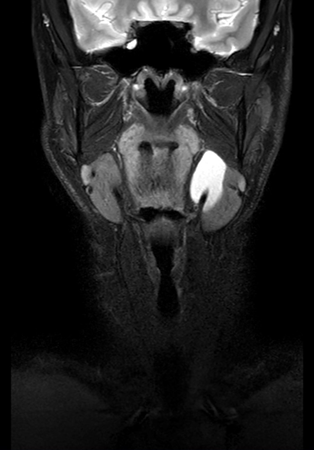

Coronal mDIXON XD - T2w TSE (Water only)

Coronal mDIXON XD - T1w TSE (Water only)